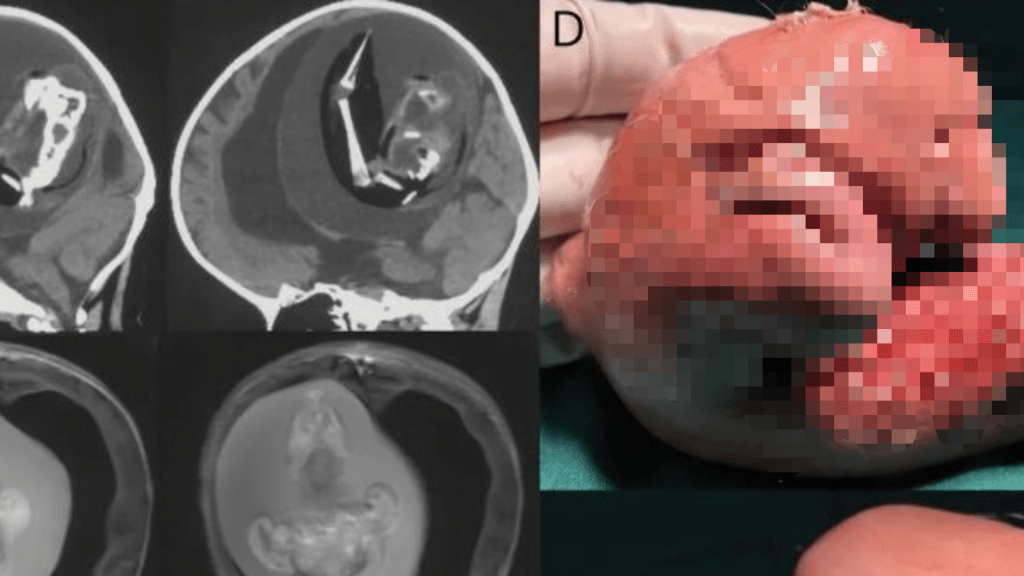

內地一名女嬰因為動作發展遲緩,被家人送往醫院檢查,經過專家診斷後發現,她的腦中居然寄生了自己的雙胞胎姊妹。這種「胎中胎」的情況極為罕見,醫學文獻上記載的病例不到200個,且僅有18例被發現寄生在兄弟姊妹的頭骨中。

報導稱,女嬰當時已經1歲,被發現有動作發展遲緩及腦積水的情況。腦積水會導致病患頭部變大、嚴重嗜睡和癲癇。專家團隊經檢查後發現,女嬰頭骨內有一個10.16公分的胎兒,而且已經長出上肢、骨骼和指甲,專家由此推測胎兒已經在女嬰的體內發育了好幾個月。

目前,醫學專家已經將胎兒從女嬰頭部中取出,但未知後續會否對孩子的健康狀況造成其他影響。